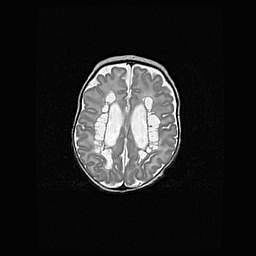

Церебральная ишемия II.

Возраст: 5 дней

Вес: 3400 г

Пол: женский

Окружность головы: 35 см

Срок гестации: 39 недель

Церебральная ишемия – это заболевание, характеризующееся недостаточностью (гипоксией) либо полным прекращением (аноксией) снабжения мозга кислородом по причине закупорки одного или нескольких сосудов. Это приводит к  что метаболическим расстройствам различной степени тяжести в тканях головного мозга, развитию коагуляционных некрозов и гибели нейронов.